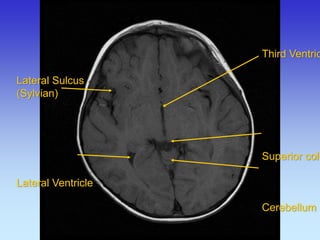

Lateral Sulcus (Sylvian) Lateral Ventricle

Third Ventricle Superior colliculus Cerebellum

Hypothalamus Inferior Colliculus